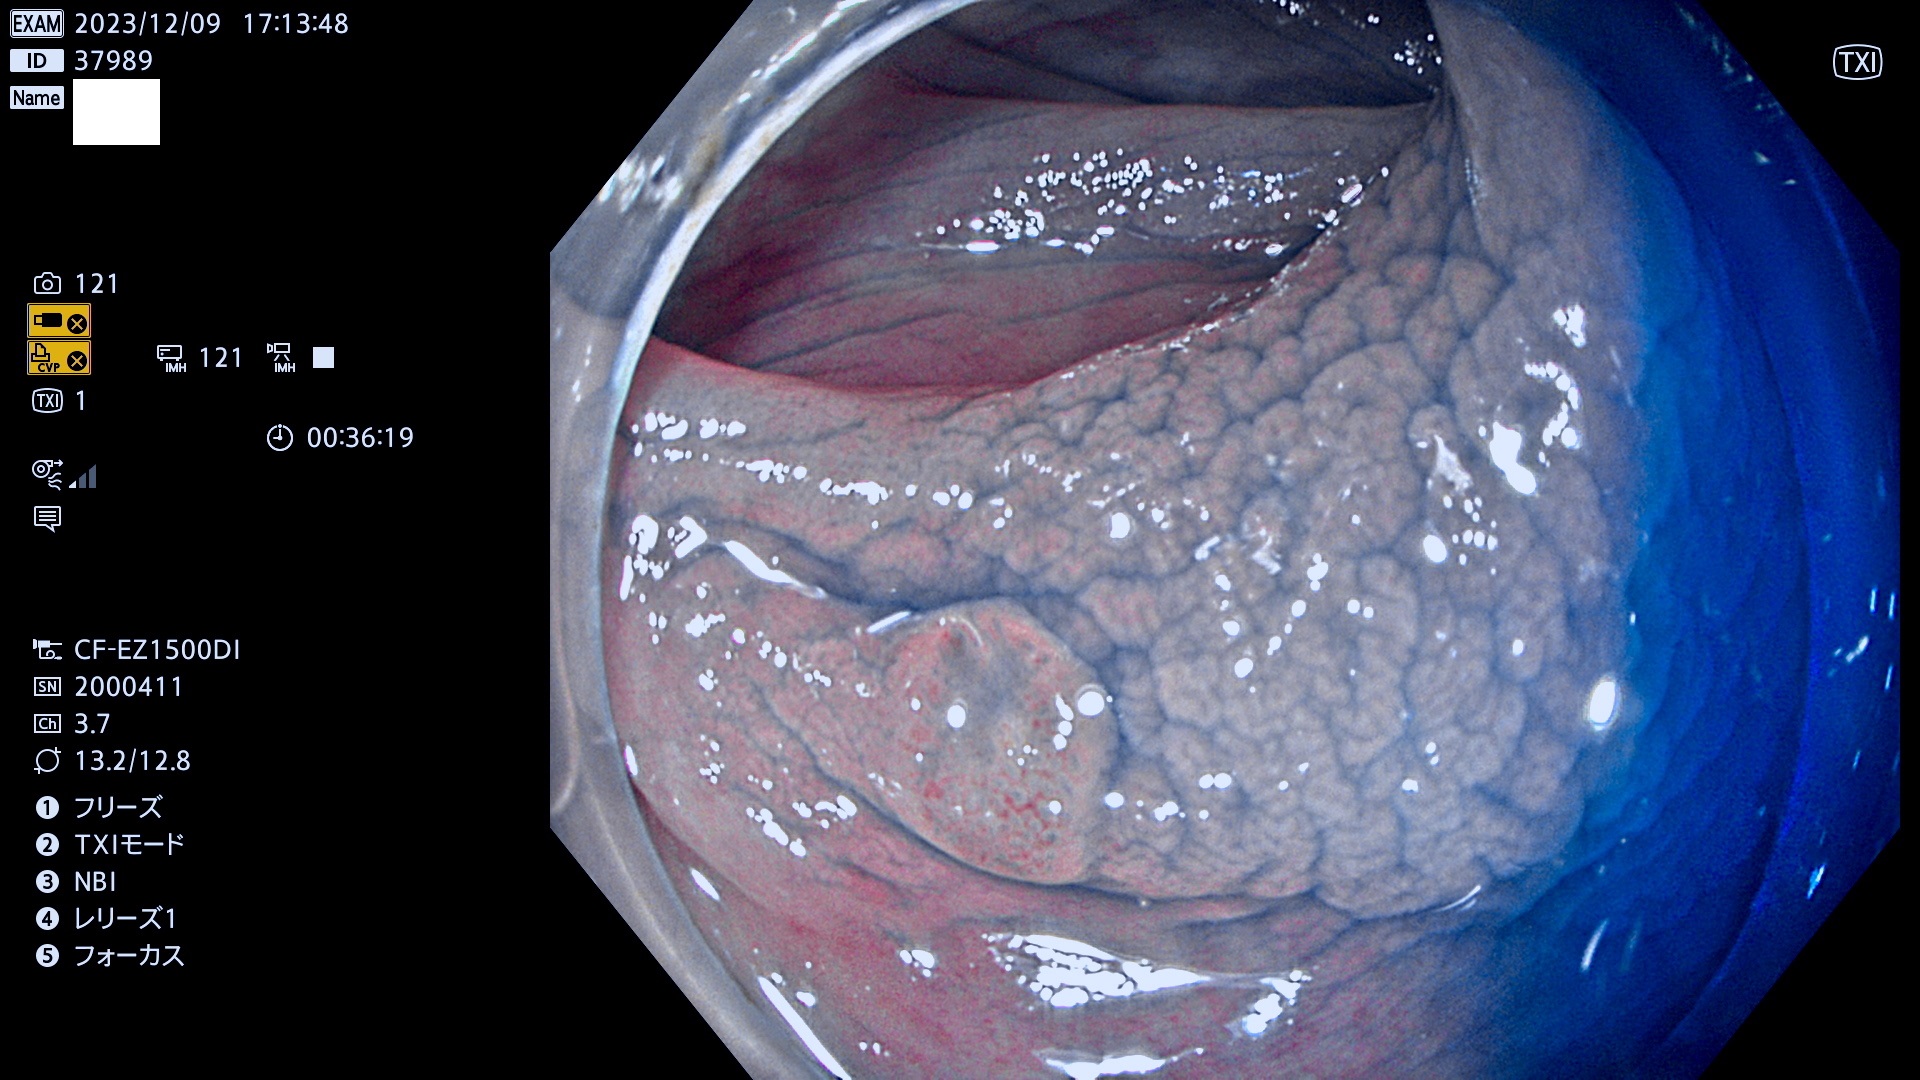

今週のUb、Uc型腺腫

表面型腺腫(Flat Adenoma)の中で、完全に平坦な物をUb、陥凹している物をUcと呼びます。平坦隆起型(Ua)よりも、発見が難しく危険な病変です。このタイプは「内視鏡後・大腸癌の重要犯人」であり、この発見率は「腺腫発見率」よりも、重要な意味があります。

毎週の検査(木・金・土・日)に発見されたUb、Uc型・腺腫を、その週の日曜の夜にUPし1週間、提示します。

抽出の対象期間 2023年12月7日(木)〜12月10(日)の4日間(48件の検査)12件